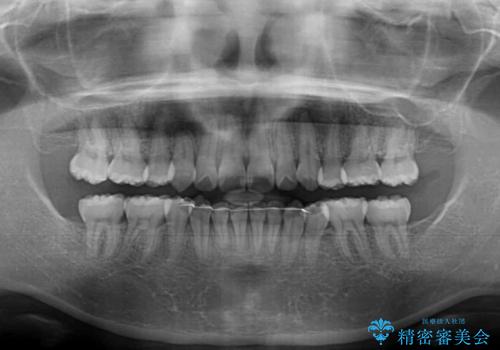

咬み合わせの乱れが著しく、治療途中で一部反対咬合となってしまいました。

アンカーなどをうまく使用して、3年の期間を要してきれいに仕上げることができました。